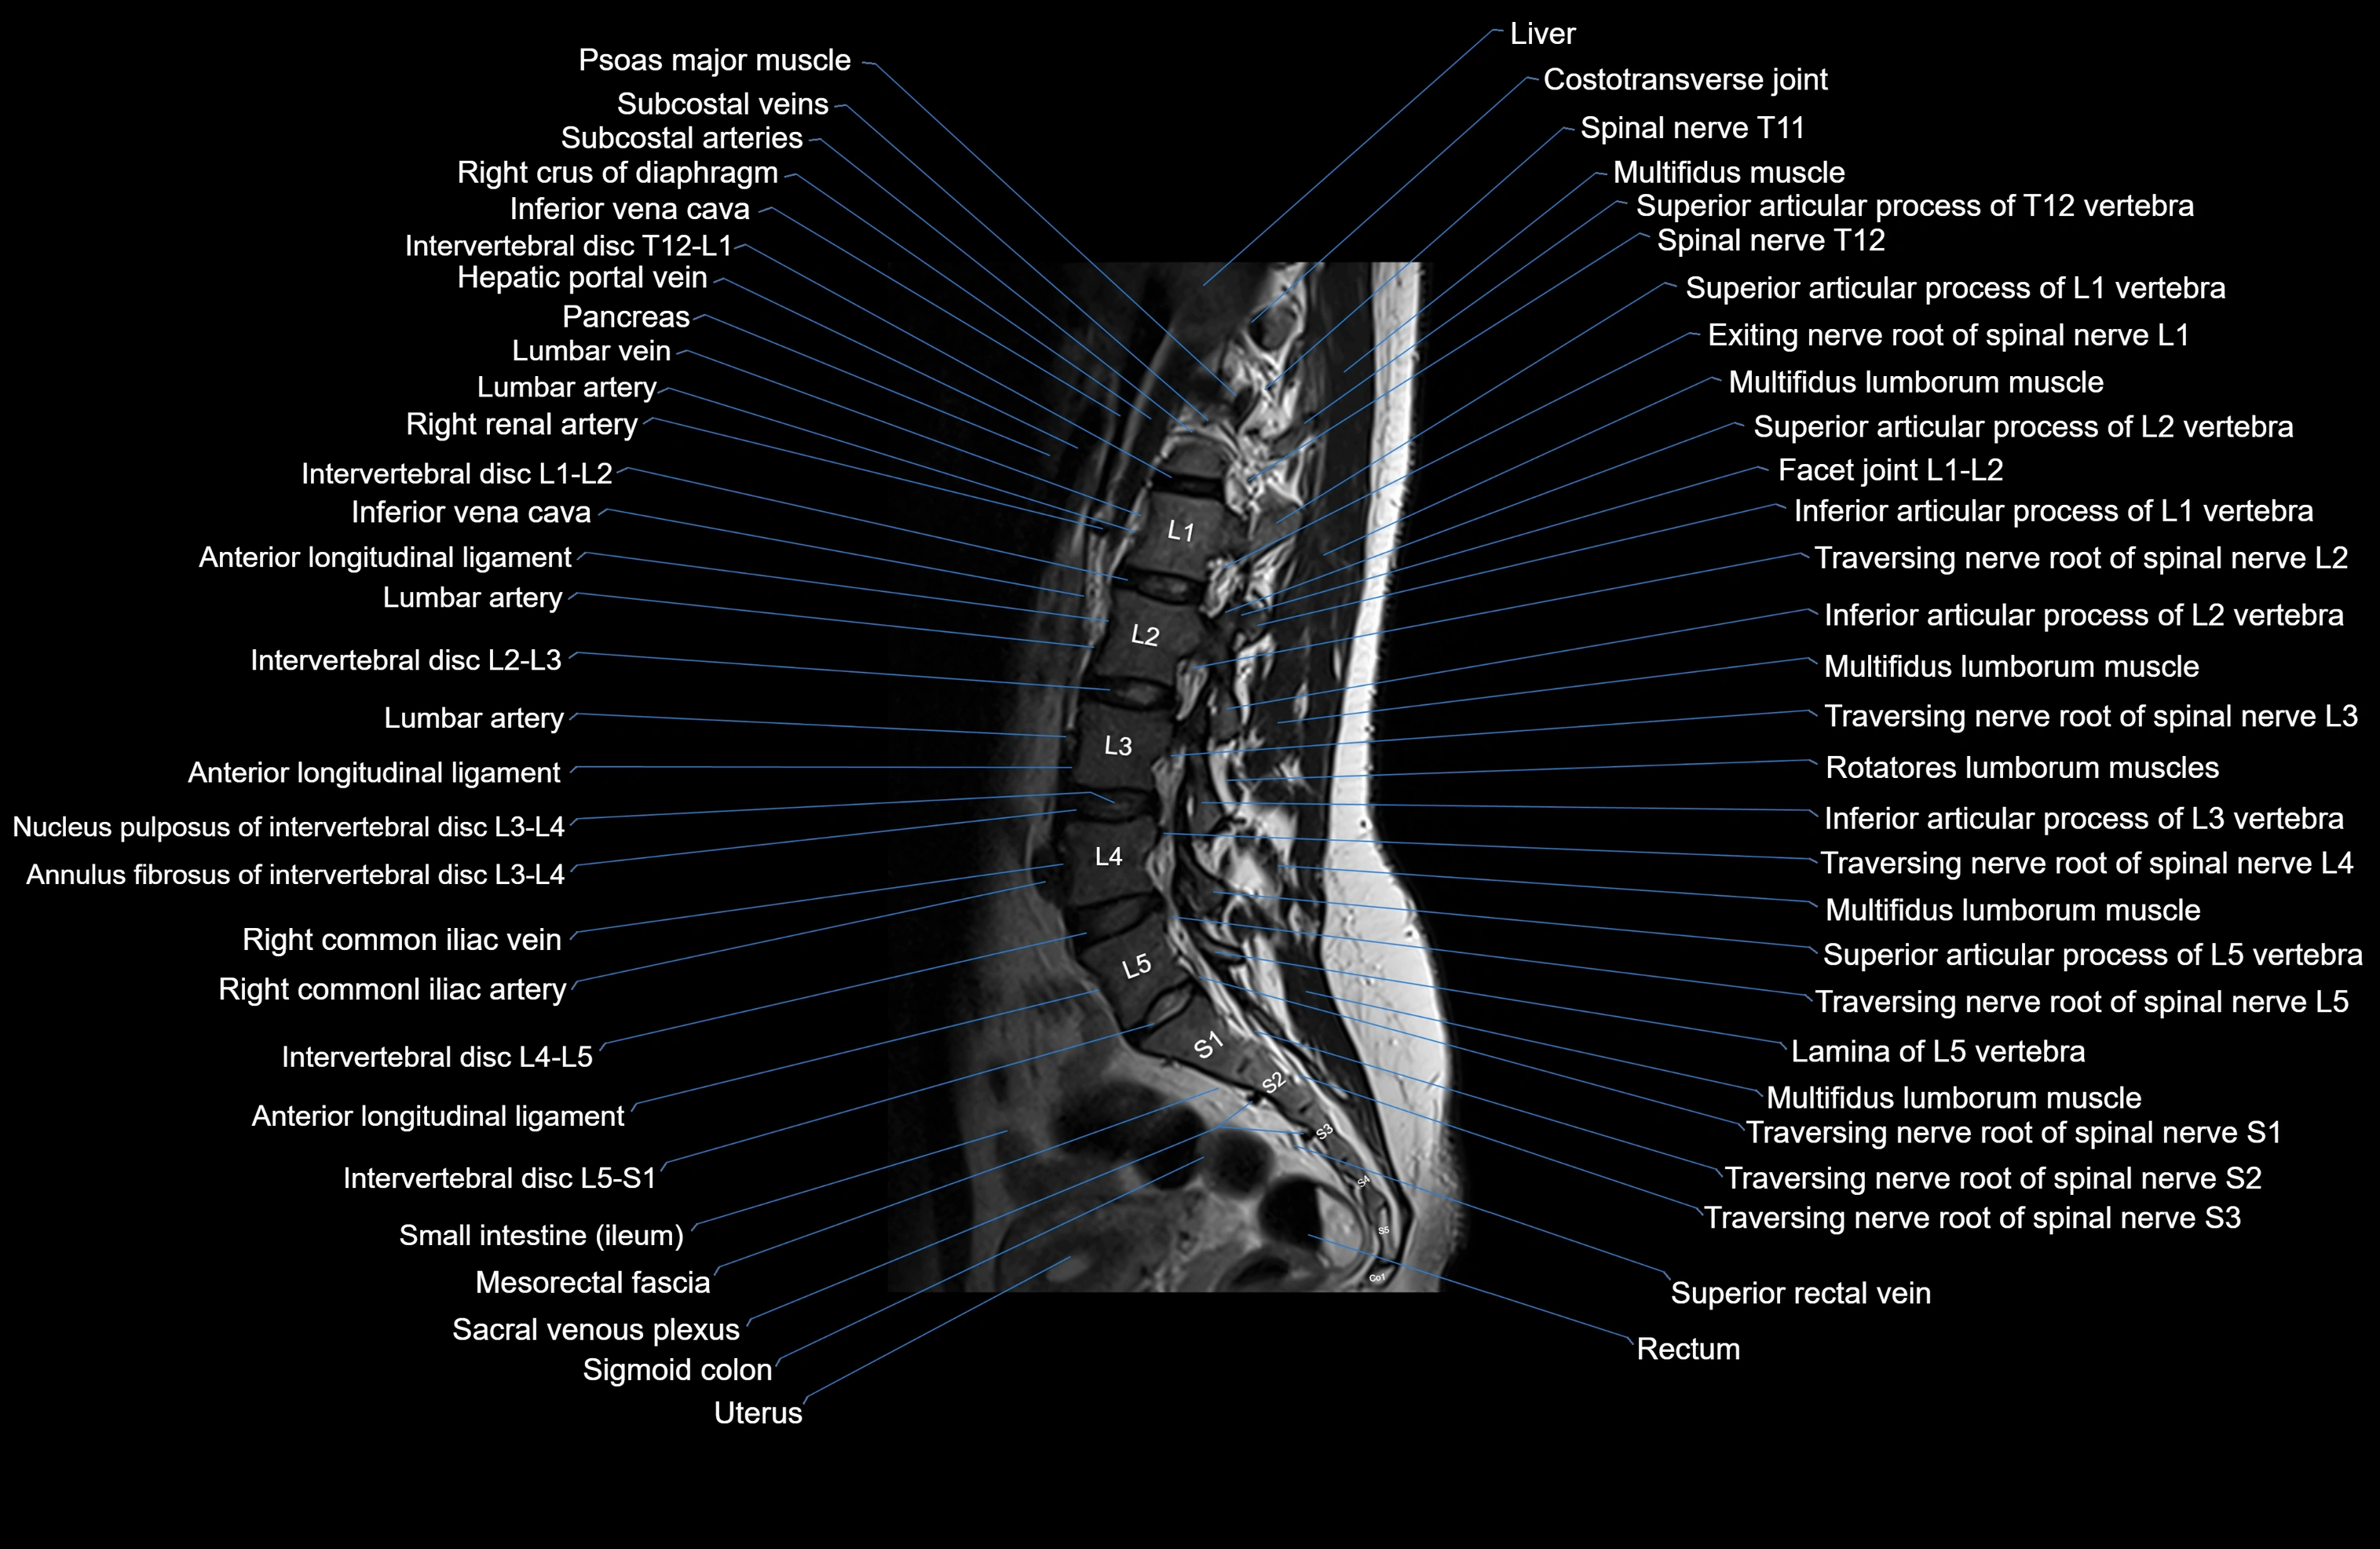

MRI images